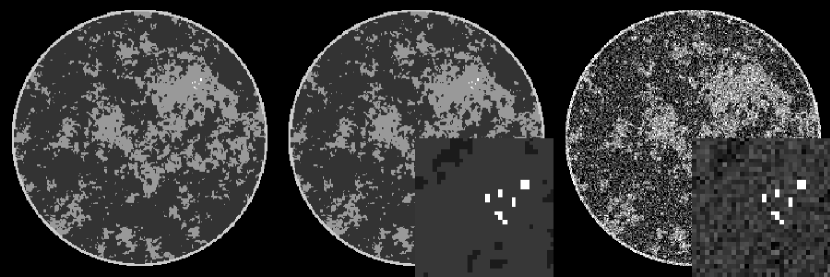

For the present case, we focus on circular, fan-beam scanning with 60 projections equally distributed over a full 360∘ angular range. The simulated radius of the X-ray source trajectory is 40cm with a source-detector distance of 80cm. The detector sampling consists of 512 bins of size 200 microns. The system matrix for the X-ray projection is computed by the line-intersection method where the matrix elements of are determined by the length of traversal in each image pixel of each source/detector-bin ray. For this phantom under ideal conditions, we have found that accurate recovery is possible with constrained, TV-minimization with as few as 50 projections. In the present study, we add Poisson noise to the data model at a level consistent with what might be expect in a typical breast CT scan. The Poisson noise model is chosen in order to investigate the impact of matching the data-error term to the noise model. For reference, the phantom is shown in Fig. 1. To have a sense of the noise level, a standard fan-beam filtered back-projection reconstruction is shown alongside the phantom for simulated Poisson noise.

For this noise model, the maximum likelihood method prescribes minimizing the KL data divergence between the available and estimated data. To gauge the importance of selecting a maximum likelihood image, we compare the results from two optimization problems: a KL data divergence plus a TV-penalty, Eq. (45) above; and a least-squares data error norm plus a TV-penalty, Eq. (32) above. With the CP framework, these two optimization problems can be easily prototyped: the solutions to both problems can be obtained without worrying about smoothing the TV semi-norm, setting algorithm parameters, or proving convergence.

For the phantom and data conditions, described above, the images for different values of the TV-penalty parameter are shown in Fig. 2. An ROI of the micro-calcification cluster is also shown. The overall and ROI images give an impression of two different visual tasks important for breast imaging: discerning the fibro-glandular tissue morphology and detection/classification of micro-calcifications. The images show some difference between the two optimization problems; most notably there is a perceptible reduction in noise in the ROIs from the KL-TV images. A firm conclusion, however, awaits a more complete study with multiple noise realizations.